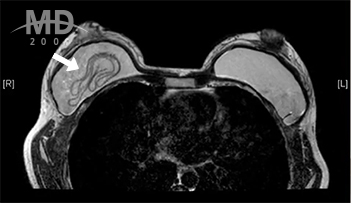

img

• 파열이 되어도 겔이 흘러 내린다거나 통증이 유발되지 않고 가슴모양도 크게 변하지 않기 때문에

자각증상으로는 파열 여부를 알기 어려우며, 정기적인 검진(초음파 검사)을 통해 발견되는 경우가 많음

• MD's Solution

• 파열된 보형물과 주변의 피막을 제거하여 깨끗한 가슴방을 만든 후 새로운 보형물로 교체함

• 유륜 또는 밑선 절개를 해야 보형물을 완전히 제거할 수 있음

* 흰색 화살표 = 파열된 보형물

• img MRI 촬영

• img 초음파 검진

보형물 파열 시 뚜렷한 자각증상이 없기 때문에 30세부터는 2년마다,

40세부터는 1년마다 정기적인 유방검진이 필수입니다!